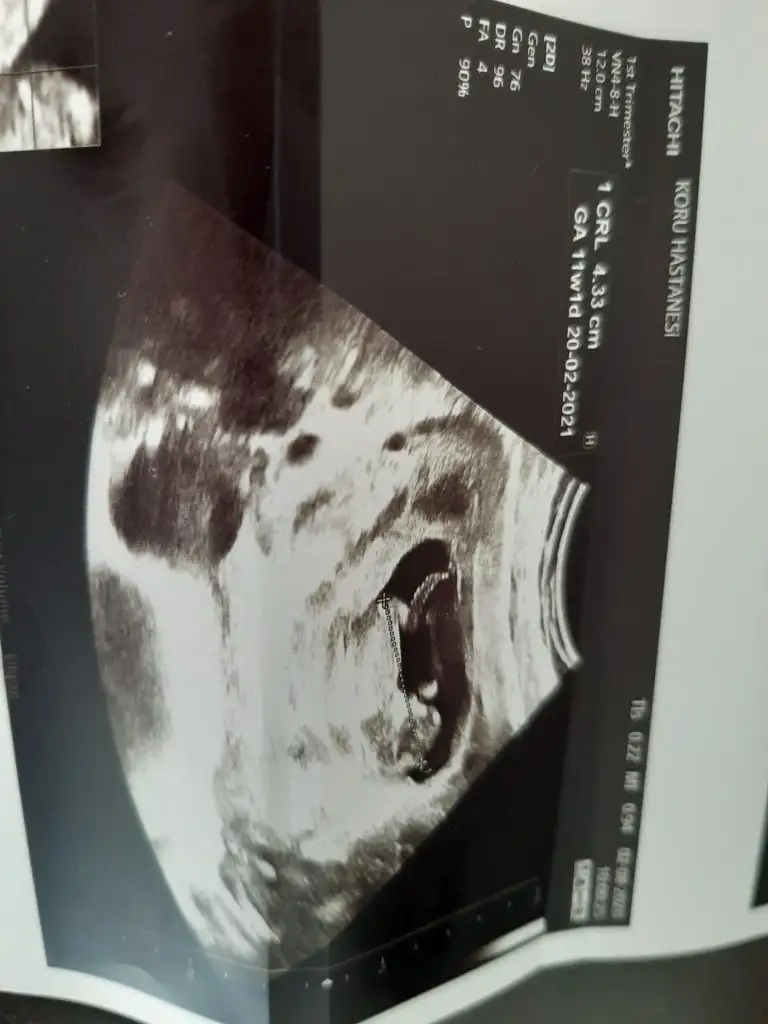

Erkeğe benzettim kafa yapısındanKızlar ilk kez bugün bebeğimi gördüm ne kadarda büyümüş çok mutlu oldumm :)

Cinsiyet tahmininden anlayan varsa tahminleri alabilirim

Bugün pazar ve bayram doktorunuz çalışıyor herhalde salı günü bizim kontrolümüzde özel devlet ultrason cihazı çok fark ediyor salı günü bende özele gideceğim Allah nasip ederseKızlar ilk kez bugün bebeğimi gördüm ne kadarda büyümüş çok mutlu oldumm :)

Bana erkek gibi geldi ama bu işi bildiğimden değil sadece öyle geldiKızlar ilk kez bugün bebeğimi gördüm ne kadarda büyümüş çok mutlu oldumm :)

Bnde erkeğe benzettimKızlar ilk kez bugün bebeğimi gördüm ne kadarda büyümüş çok mutlu oldumm :)